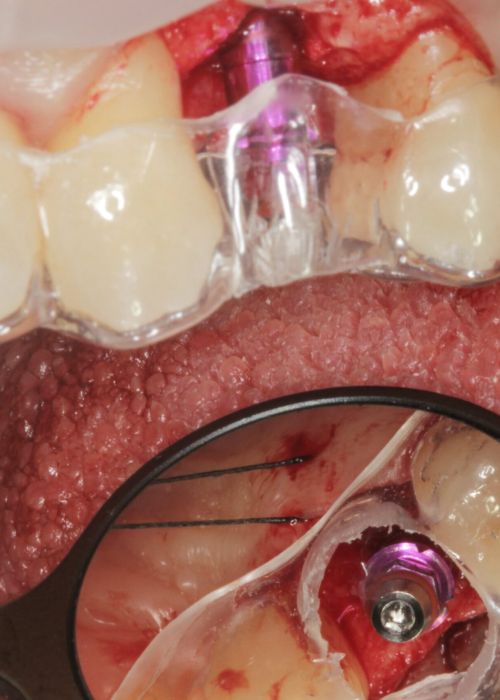

Resolución de un caso con implicación estética en el sector antero-superior. A propósito de un caso

Explantación de implante mal posicionado en sector estético y regeneración posterior con injerto en bloque

Implant explantation poorly positioned in an aesthetic sector and subsequent regeneration with block grafting. Clinical case